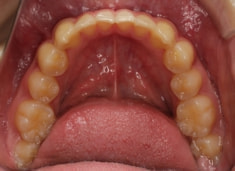

上下顎のギャップはありますが、顔面自体の幅径は良好な値を示していますので、スペース不足は拡大することによって解決できポテンシャルはあると考えられます。

検査時のレントゲン分析では、上下顎の関係は、上顎の劣成長があり下顎前突傾向という値がでておりましたが、前歯ジャンプ後はフェイスマスクの効果もあり、上下顎の関係は正常化しています。

上顎が若干優位になっていますので、今後の下顎の成長のための貯金になっているくらいです。